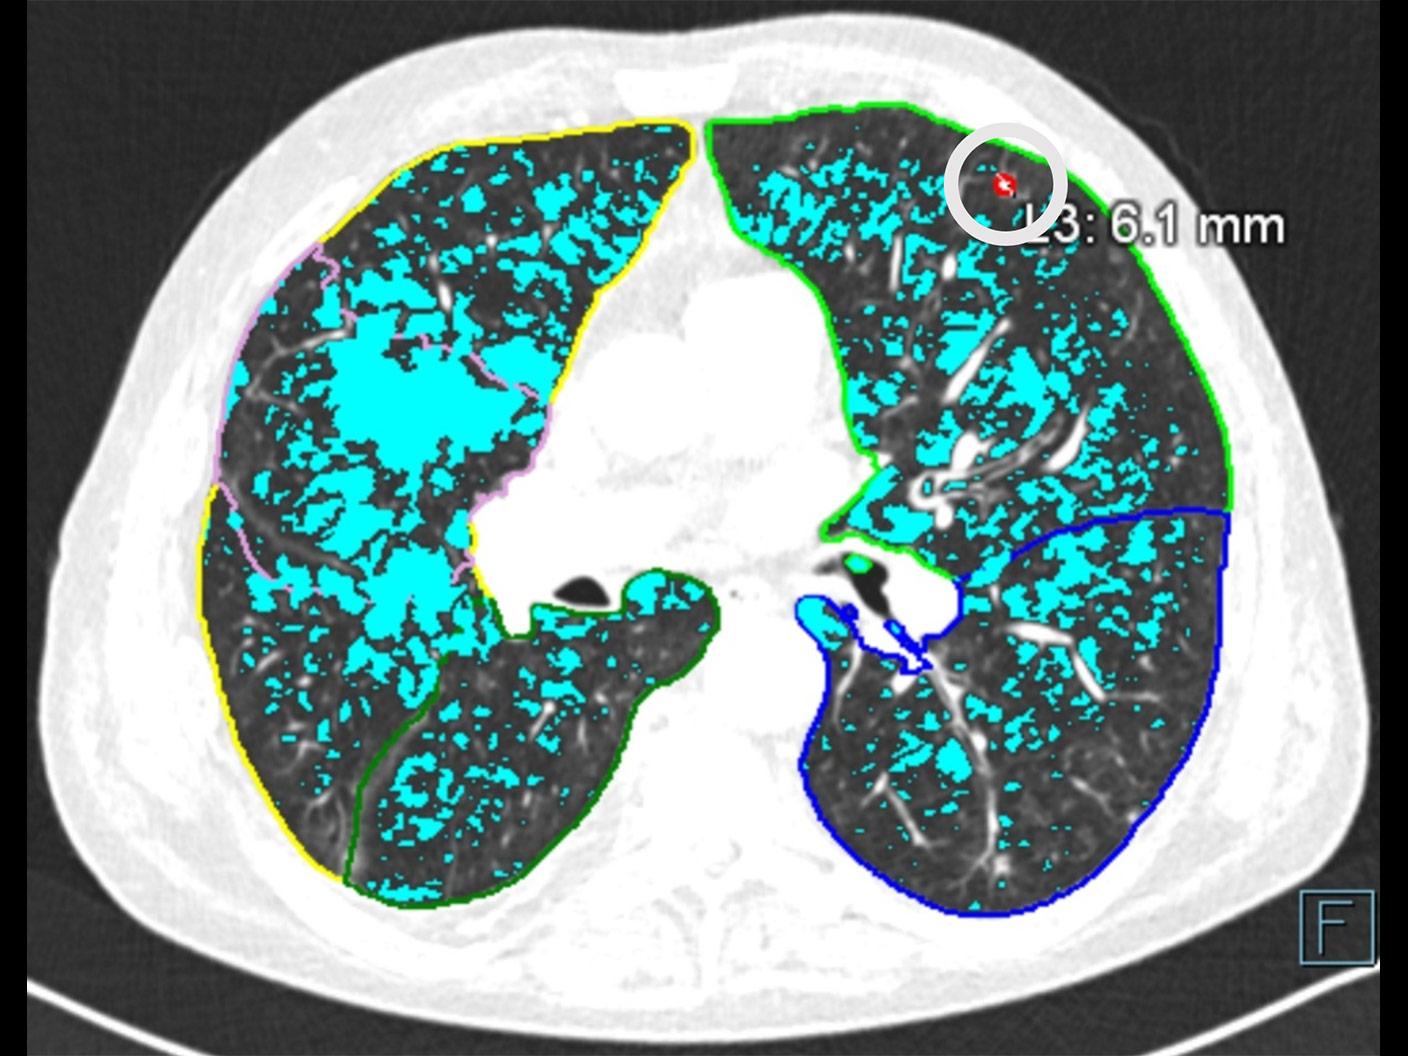

With a mobile lung cancer screening program, you can bring the low-dose CT exam that at-risk patients need closer to where they live. With a short set-up, our self-contained Mobile Lung Screening Solution with a SOMATOM go.Up CT scanner offers the high image quality, ease of use, and flexibility you need to create a lung screening program that meets the real-life needs of your community.